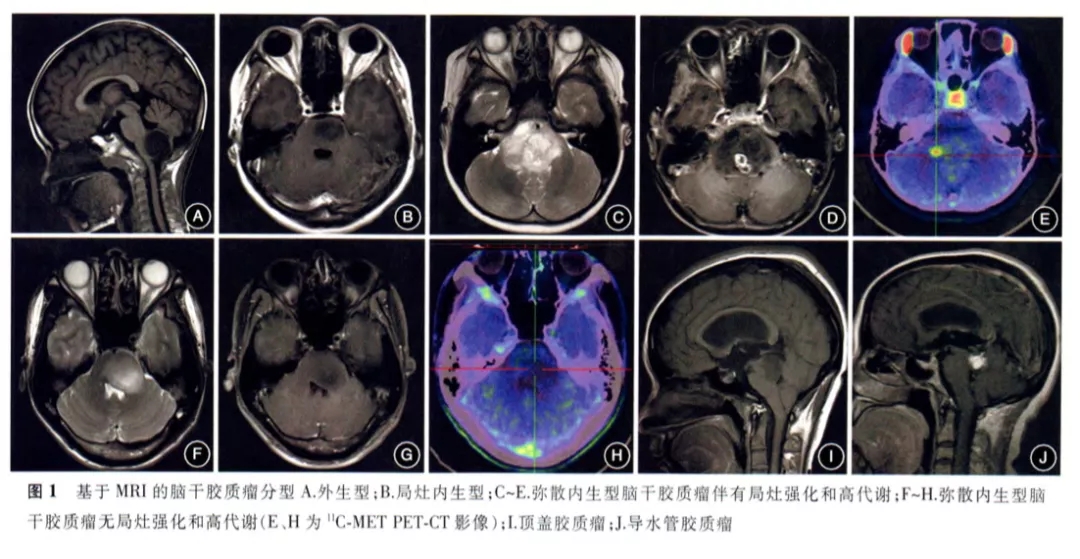

根据MR影像特点的脑干胶质瘤分型:

Ⅰ型:外生型脑干胶质瘤,肿瘤向外生长,主体位于脑干外部(图1A) 。

Ⅱ型:内生型脑干胶质瘤,可分为Ⅱa型即局灶内生型(图1B)和Ⅱb型即弥散内生型。对Ⅱb型脑干胶质瘤建议行11C-MET PET检查,综合MRI增强扫描的特点和 MET摄取情况,可将Ⅱb型肿瘤分为伴有局灶性强化或高代谢的Ⅱb1型(图1 C~E)和无局灶性强化或高代谢的Ⅱb2型。

Ⅲ型:为不同类型的脑干胶质瘤,Ⅲa型为顶盖胶质瘤(图1I);Ⅲb型为导水管胶质瘤,其发生率较低,以梗阻性脑积水为首发症状,病理类型以低级别胶质瘤为主(图1J);Ⅲc型为NF1相关的脑干胶质瘤,可分布在脑干内任何部位,可表现出各种生长方式和影像学特点。